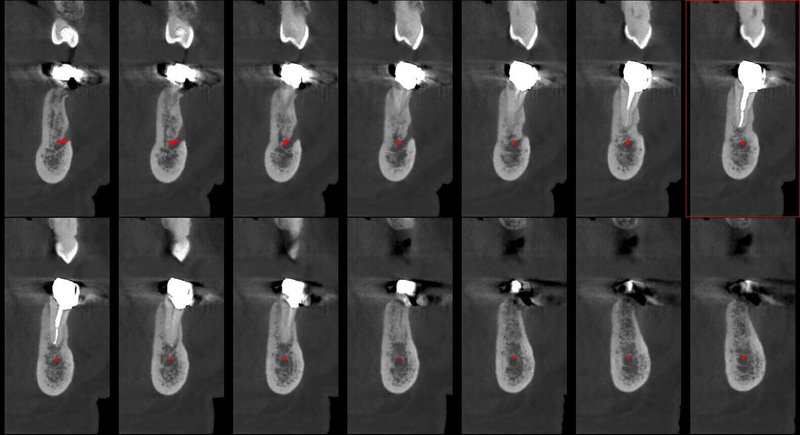

- Мощная диагностика

- Технология HR от Newtom

GIANO HR – универсальное обновляемое устройство от NewTom для всех задач, связанных с радиографией. Благодаря полному диапазону опций 2D и 3D исследования для стоматологии оно предлагает множество особых трехмерных обследований для челюстно-лицевой хирургии, оториноларингологии и осмотра шейного отдела позвоночника. Визуализация только наивысшего качества с технологиями и опытом NewTom

NNT – программное обеспечение NewTom, предоставляющее несколько специальных режимов применения для имплантологии, эндодонтии, пародонтологии, челюстно-лицевой хирургии и радиографии. Это мощное технологически новейшее устройство, разработанное, чтобы снимать и обрабатывать изображения в несколько простых шагов для получения информации, необходимой для конкретного подробного диагноза пациенту. Продвинутое устройство, дающее врачу специальные инструменты для измерения анатомической области (расстояния и углы), нахождения нижнего альвеолярного нерва и замера объема верхних дыхательных путей.